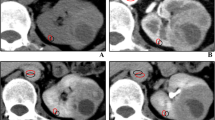

Area under the ROC curves (AUC) of entropy at fine, medium, and coarse spatial filters were 0.804 with a 95% confidence interval of 0.755–0.848, 0.841 (0.803–0.888), and 0.822 (0.774–0.864), respectively (Fig. 4). Entropy greater than 5.34 at medium spatial filter had sensitivity and specificity of 77.5% and 83.7%, respectively, for diagnosing ccRCC.

ROC curves plotting sensitivity (y-axis) and 1-specificity (x-axis) of entropy at different spatial filters in differentiating ccRCC from pRCC. Entropy 2, entropy at fine spatial filter (SSF = 2 mm); entropy 4, entropy at medium spatial filter (SSF = 4 mm); entropy 6, entropy at coarse spatial filter (SSF = 6 mm). Area under ROC curves (AUC) are given in the text